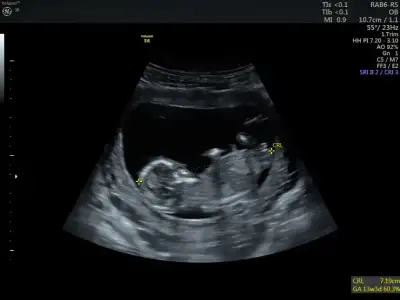

Heyecanla cevabını bekliyoruzMerhabaIkra meyra benim de bebeğimin fotoğrafı bu şekilde. 11+4 deyiz :) doktor göremedim ama acaba nubunu görebilir misiniz?

Erkek sanki 12-13 olursa paylaşınmerhabaIkra meyra 11+1 karından ultrasyon fotografım cinsiyet hakkında bir yorumda bulunursan çok sevinirim

Erkek sanki 12-13 olursa paylaşınMerhabaIkra meyra benim de bebeğimin fotoğrafı bu şekilde. 11+4 deyiz :) doktor göremedim ama acaba nubunu görebilir misiniz?

Kız gibi sanki emin olamadım13 haftalık cinsiyet tahmini yapabilir misiniz?Ikra meyra

USG yarım almis Dr11+3 bebeğimin ultrason görüntüsüIkra meyra tahmin edebilir misiniz